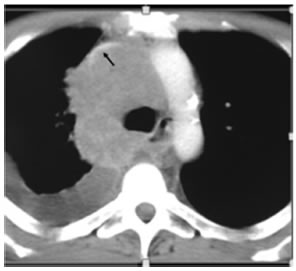

El síndrome de vena cava superior (SVCS) relacionado con la malignidad es generalmente debido a la compresión por un tumor voluminoso o la formación de trombos intraluminales tumorales. El cáncer de pulmón es la causa más común del SVCS1. Representa el 65-80% de los casos según diferentes series publicadas2. Tanto la masa tumoral como las metástasis mediastinales pueden comprimir la vena cava. El SVCS es más frecuente en pacientes con cáncer de pulmón de células pequeñas (CPCP) que en pacientes con cáncer de pulmón no pequeñas células (CPNPC). En el momento del diagnóstico, el SVCS puede ser observado en 10% de los pacientes con CPCP y en 1.7% de los pacientes con CPNPC3. Otras causas pueden ser linfoma, tumores del timo, cáncer de esófago o enfermedad metastásica de un tumor primario extratorácico. La presencia de edema en esclavina y disnea son características típicas del SVCS. La circulación colateral se produce en los sistemas venosos de la ácigos, intercostales, mediastinal, paravertebral, hemiácigos, toracoacromioclavicular y transhepática, (fístula sistémico-portal). Estas vías colaterales pueden ponerse mejor en evidencia con reconstrucciones multiplanares y tridimensionales4. Los signos de alerta de severidad del SVCS incluyen estridor (que puede indicar la presencia de edema laríngeo), confusión y obnubilación (por edema cerebral).

La tomografía computarizada con contraste endovenoso es la prueba más comúnmente utilizada para el diagnóstico de la obstrucción de vena cava superior (OVCS). Permite, en general, el diagnóstico preciso y puede mostrar el grado, nivel y causa de la misma. La presencia de vasos colaterales dilatados es altamente sugestiva de OVCS, con una sensibilidad del 96% y una especificidad del 92%4, 5. La venografía por resonancia magnética es una alternativa que está siendo utilizada cada vez más. Tiene una sensibilidad y especificidad del 100% así como gran precisión para evaluar las grandes venas centrales6, 7.

Agradecimientos: Agradecemos al Dr. Juan Carlos Spina (Hospital Británico de Buenos Aires) por el aporte de la imagen del síndrome de vena cava superior.